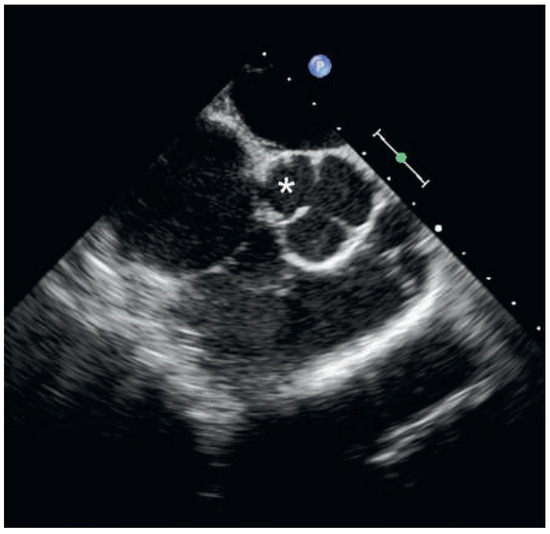

Infarct or Pericarditis?

by Sebastian Rogowski, Flurina Arquint, Hans Rickli, Niklas F. Ehl and Micha T. Maeder

Cardiovasc. Med. 2015, 18(3), 107; https://doi.org/10.4414/cvm.2015.00314 - 18 Mar 2015

A 56-year-old man was referred at 5 a.m. with severe central chest pain radiating into the left arm, which had awoken him from sleep one hour previously [...] Full article